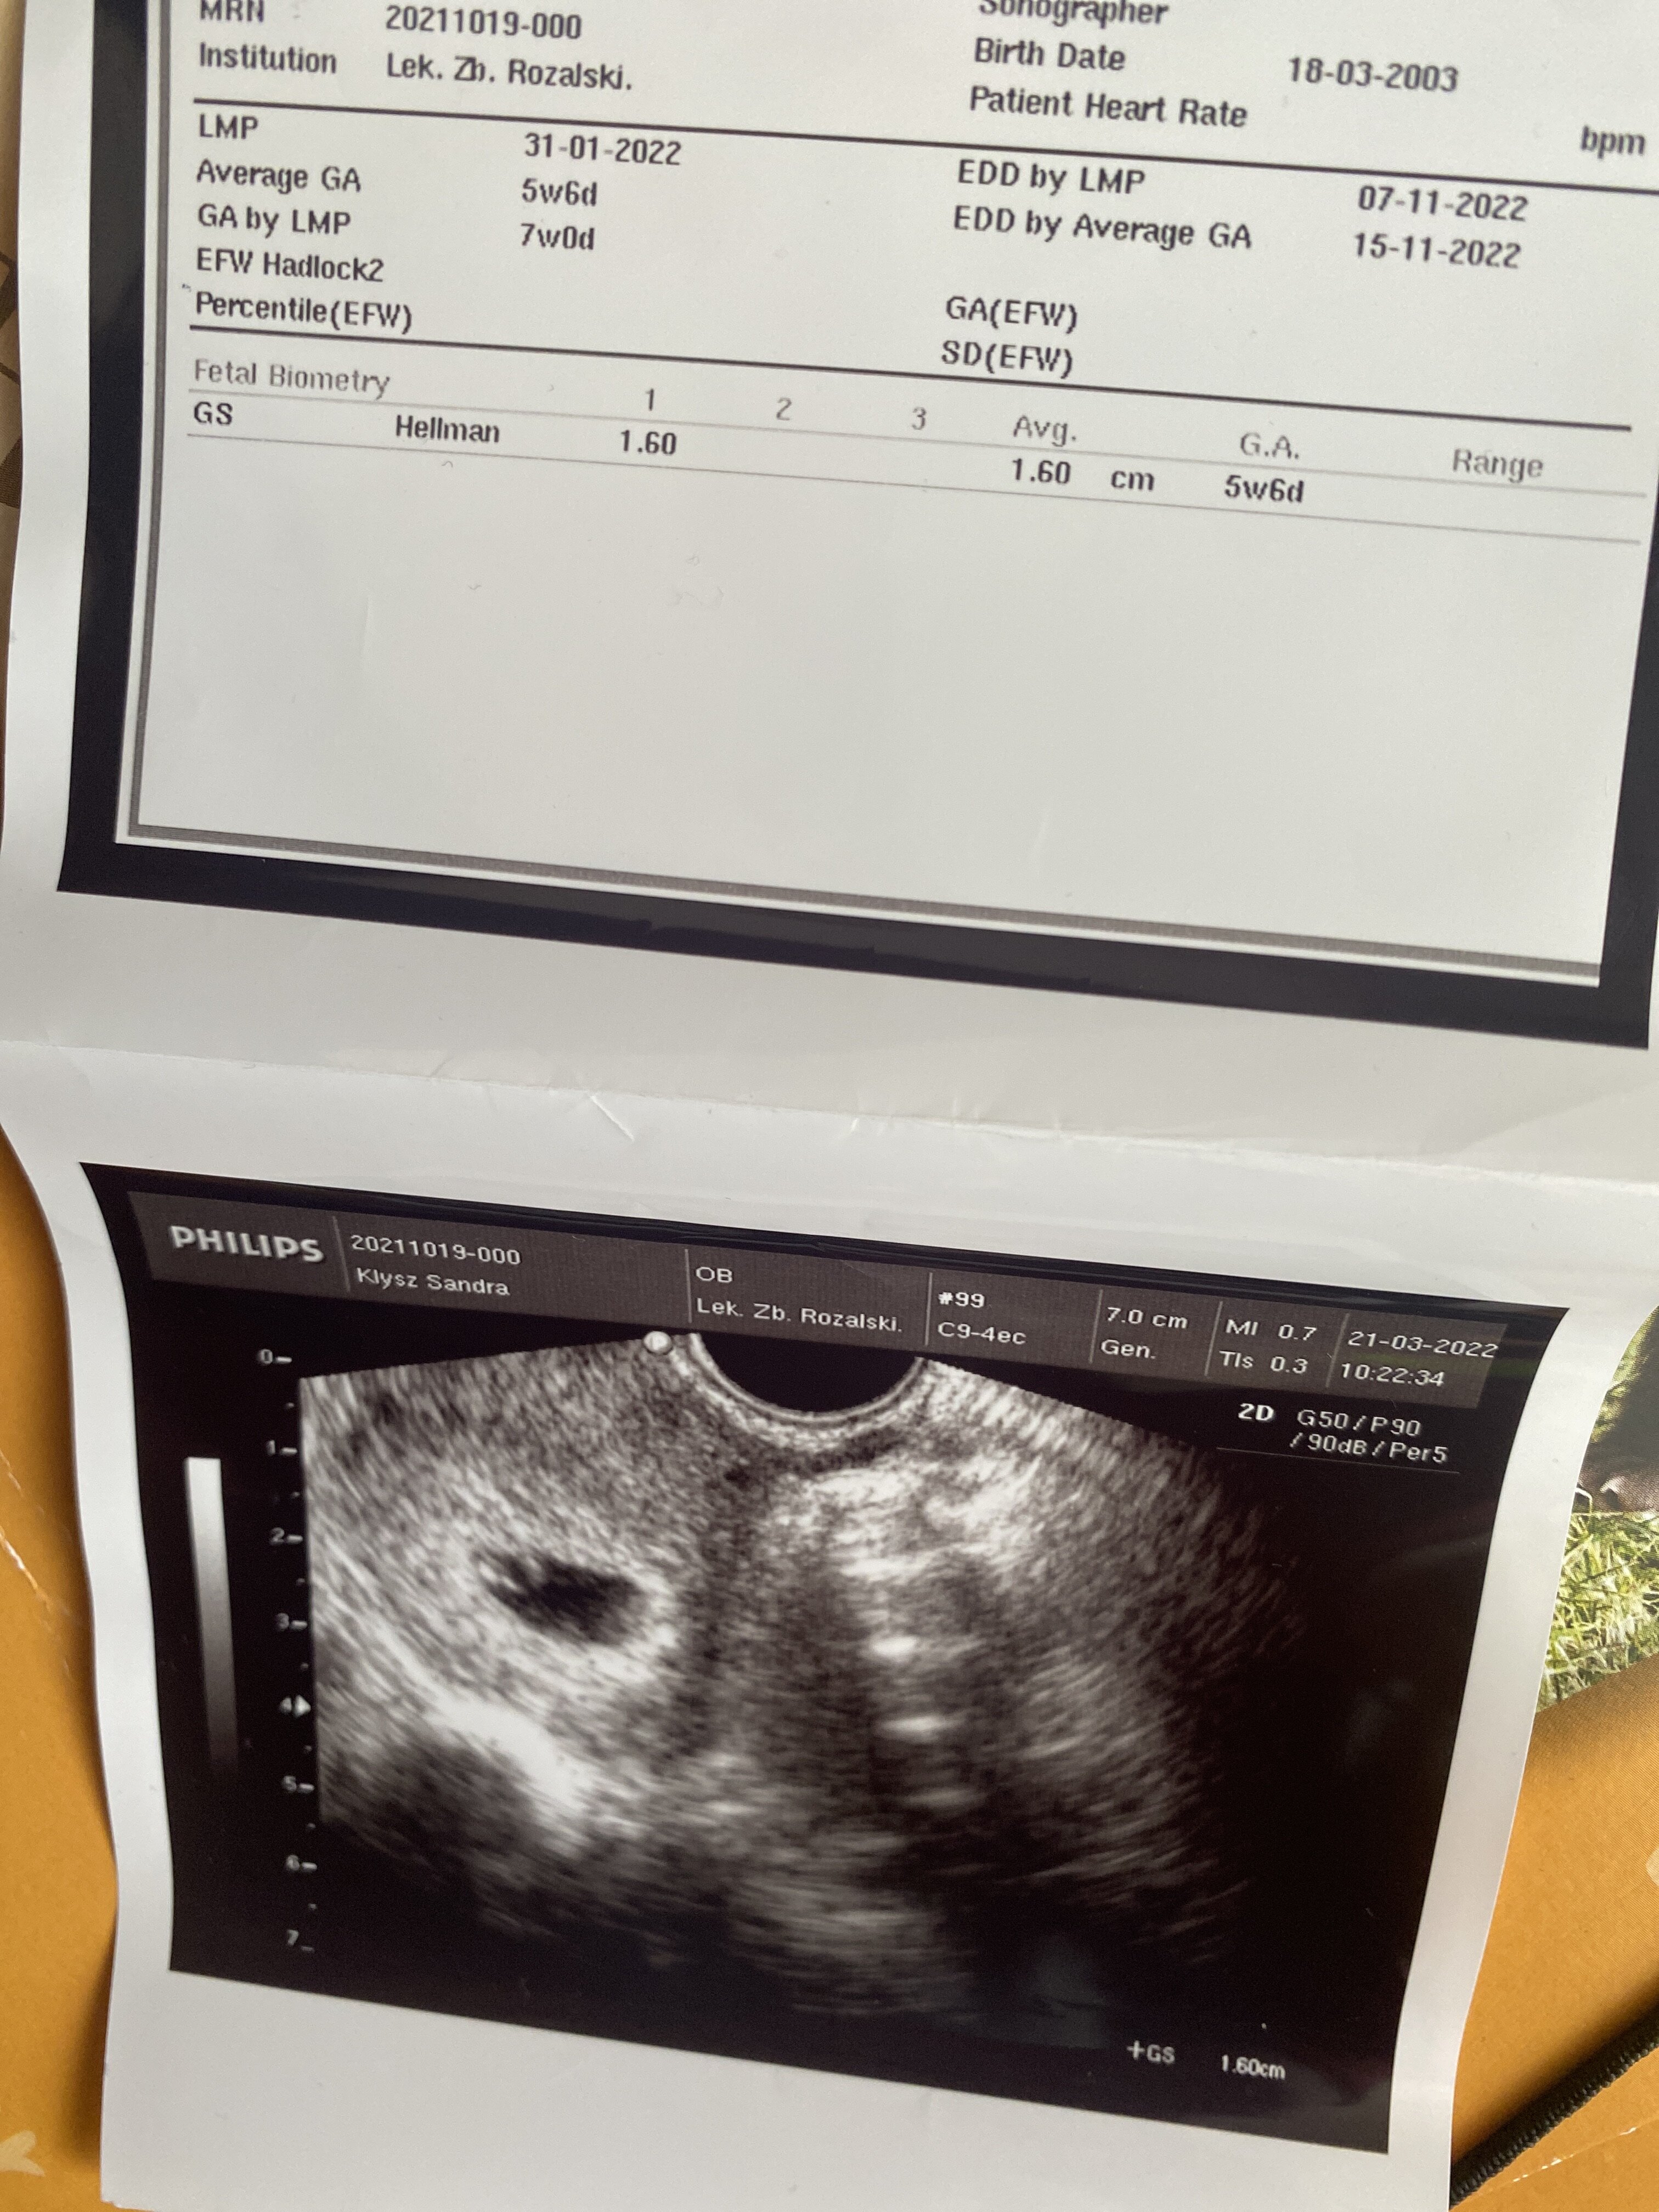

Czy wszytsko jest okej? W 7 tyg nie było widać zarodka

Załączniki

• image.jpg

image.jpg

1,7 MB · Wyświetleń: 82